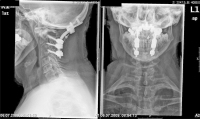

Abbildung 1: Sagittales Computertomogramm mit Darstellung einer atlanto-axialen Instabilität und signifikanter Einengung des Zervikalkanals in Höhe von HWK 1/2.

Keywords: atlanto-axiale InstabilitätComputertomogrammCTEinengung des Zervikalkanals